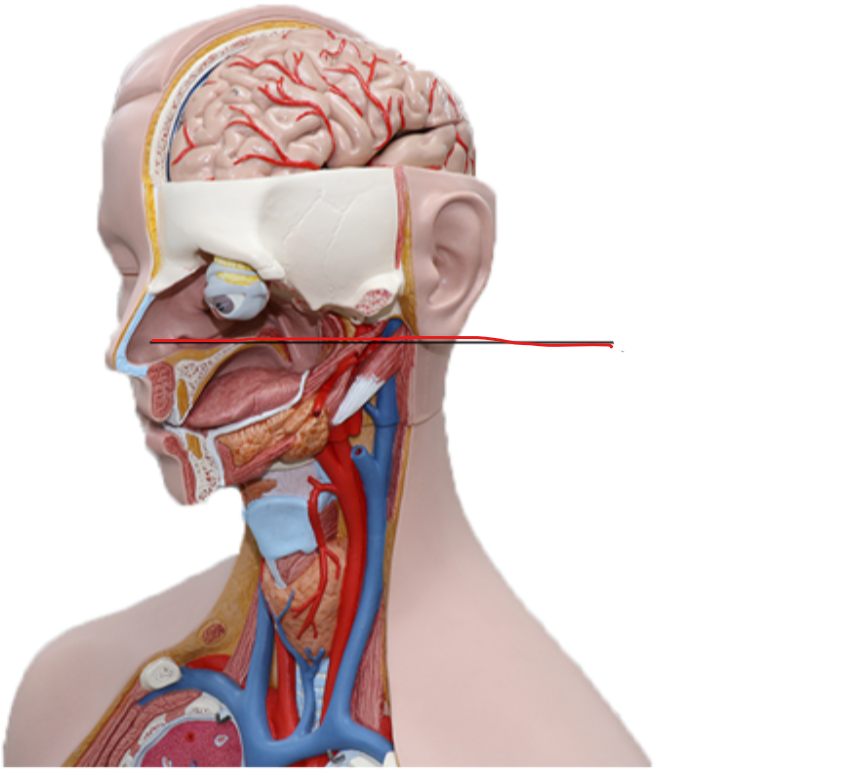

What structure is this?

Hard Palate

What structure is this?

Soft Palate

What structure is this?

Uvula

Nasal cavity

Superior Nasal Concha

Middle Nasal Concha

Inferior Nasal Concha

The nasopharynx region of the pharynx

The Oropharynx region of the pharynx

The Laryngopharynx region of the pharynx

Thyroid Cartilage

Cricothyroid Ligament

Cricoid Cartilage

Epiglottis

Trachea

Tracheal Cartilage

The pharynx

Larynx

What are the three laryngeal cartilages?

epiglottis, cricoid and thyroid cartilage

Nasal Septum